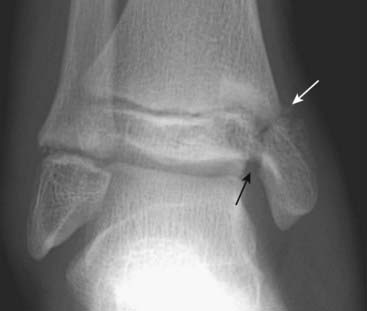

Figure 22-16 Salter-Harris III fracture.

With type III fractures, a fracture of the epiphyseal plate as well as a longitudinal fracture through the epiphysis itself is seen (solid white arrow), which means the fracture invariably enters the joint space and fractures the articular cartilage. This can have long-term implications for the development of secondary osteoarthritis and can result in asymmetric and premature fusion of the growth plate with subsequent deformity of the bone.